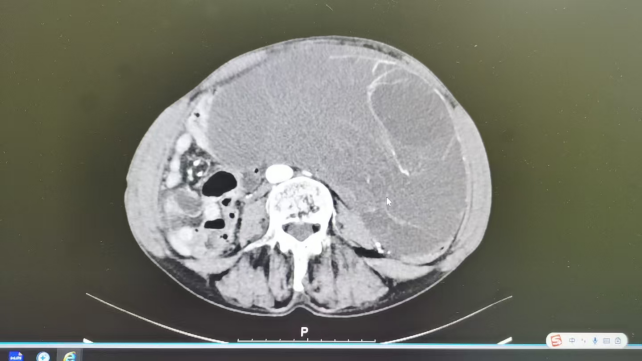

69岁的王大娘,曾经历两次胆囊手术,此次因“恶心、呕吐、纳差1天”紧急入院,检查发现腹腔内存在巨大囊实性占位,病情复杂且危重。

面对传统开腹手术创伤大、恢复慢,对高龄患者风险极高的困境,晋城市人民医院赵淑云团队果断选择经脐单孔腹腔镜技术,仅通过4厘米的脐部切口,精准地完成了子宫及双侧附件切除术。术中病理确诊为卵巢浆粘液性囊腺瘤,整个手术仅耗时2小时,展现了超高的手术效率与精准度。